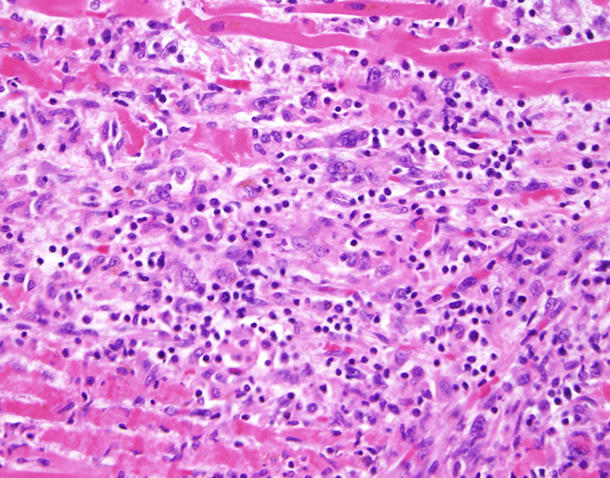

Tejido cardíaco de un paciente tratado con un inhibidor de puntos de control inmunitario que muestra células T (puntos azules) que invaden las fibras musculares en el corazón.

Fuente: Doctor Javid Moslehi, Universidad de Vanderbilt

Un reciente estudio demostró que un pequeño porcentaje de pacientes que reciben fármacos de inmunoterapia denominados inhibidores de puntos de control inmunitario, presentan la inflamación del músculo cardíaco denominada miocarditis. En ese estudio, casi la mitad de los pacientes que padecieron miocarditis grave, murieron debido a esta complicación.

"En un número pequeño pero significativo de pacientes, se presenta un desenlace mortal por el uso de inhibidores de puntos de control inmunitario que está relacionado directamente con el corazón", dijo el doctor Javid Moslehi, quien dirige el Programa de Cardioncología del Centro Oncológico Vanderbilt-Ingram y estuvo a cargo del estudio. (Otros estudios han estimado que la incidencia de miocarditis en pacientes que reciben inhibidores de puntos de control es alrededor de 1 %.)